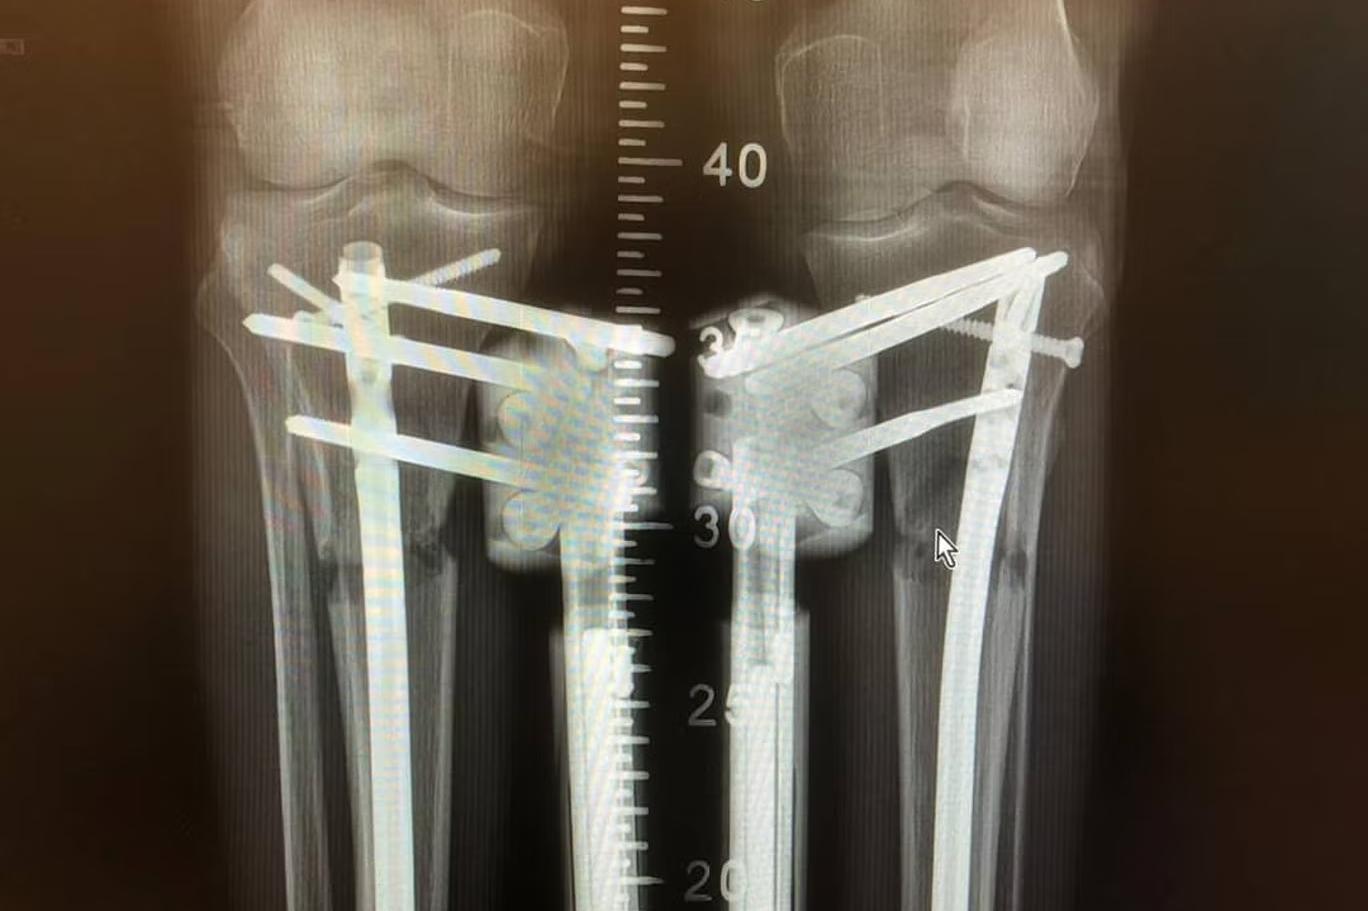

اس آپریشن کے بعد مکمل صحت یاب ہونے میں 80 دن سے زیادہ وقت لگتا ہے (Wanna Be Taller)

اس سے ران کی ہڈی میں ایک راستہ بنتا ہے جہاں ایک اندرونی لمبا کیل جڑ دیا جاتا ہے اور اسے پختہ کرنے کے لیے فریکچر کے اوپر اور نیچے ڈرل کر کے پیچ لگا دیے جاتے ہیں۔

پیچ کولہے سے ذرا نیچے اور گھٹنے سے اوپر ہوتے ہیں۔ سرجری کے بعد ریموٹ کنٹرول سے مقناطیسی سینسر چلائے جاتے ہیں تاکہ کیل کو تقریباً 1 ملی میٹر روزانہ کی رفتار سے بڑھایا جا سکے۔

جسم خالی جگہ کو پُر کرنے کے لیے نئی ہڈی پیدا کر کے اپنا ردعمل ظاہر کرتا ہے اور اس طرح تقریباً 80 دنوں کے عرصے میں فریکچر کے کنارے فاصلہ پاٹتے ہوئے نئی ہڈی کی صورت اختیار کر لیتے ہیں جس کی لمبائی عام طور پر دو سے تین انچ ہوتی ہے۔

ایل او این طریقہ اب بھی الیزاروف کی ایک تیکنیک  استعمال کرتا ہے، ایک قسم کا بیرونی فکسیٹر یا دھاتی فریم جو باہر سے ٹانگ کے گرد لپیٹا جاتا ہے اور پنیں لگا کر جلد کے ذریعے ہڈی سے منسلک کر دیا جاتا ہے۔

اس کے بعد ہوٹل میں دی جانی والی دیکھ بھال انتہائی اہمیت کی حامل ہے۔ جانا بتاتی ہیں کہ روزانہ کی سخت فزیوتھراپی اور سٹریچنگ ایکسرسائز کے ساتھ ساتھ  مریض کو ہر 15 دن میں ایکس رے کی ضرورت ہوتی ہے تاکہ یہ یقینی بنایا جا سکے کہ پہلے والی ہڈیاں نئی ہڈی بننے کی رفتار کی نسبت زیادہ تیزی سے الگ تو نہیں ہو رہیں۔